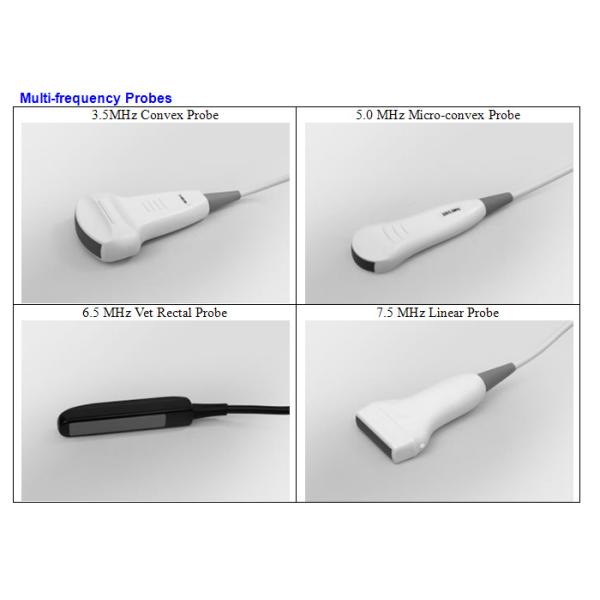

The full digital veterinary ultrasound scanner comes with several optional probes to meet the needs

in clinical diagnosis. It is equipped with PAL-D video output function to take the advantage of external video printers and large screen displays.

| Scanning Mode | Convex/linear/Micro-convex |

| Standard Configuration | 6.5MHz Vet Rectal Linear Probe |

| Optional Configuration | 3.5MHz Convex Probe |

| 7.5MHz HF Linear Probe | |

| 5.0MHz Micro-Convex Probe | |